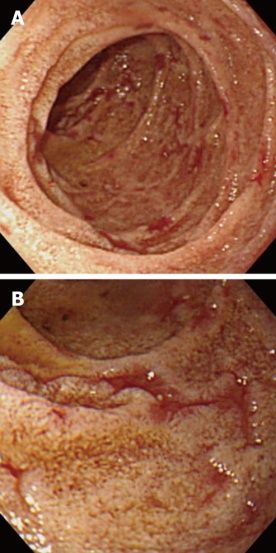

Рисунок 5. AL-амилоидоз [9].

Колоноскопия выявила два типа язвенных поражений в поперечной ободочной кишке: язву неправильной формы с подслизистой гематомой (A, B) и резко очерченную язву с небольшой подслизистой гематомой (C, D). Предполагают, что такой полиморфизм изменений отражает время возникновения дефектов слизистой толстой кишки при AL-амилоидозе. Следует считать гематому первичной по отношению к язве (B, D — хромоскопия с индигокармином). ##это подрисуночная подпись##